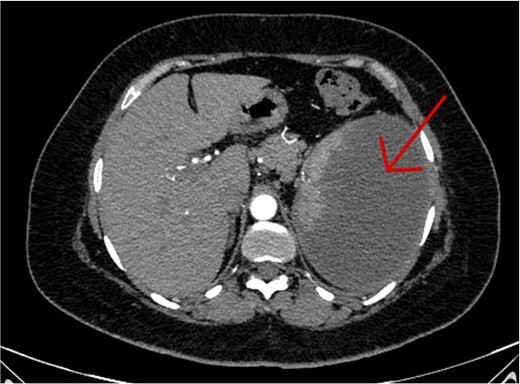

The CT scan confirmed a Dieulafoy’s lesion from the left phrenic artery (Fig. 2a and b) and showed collateral vascular channels around the pancreas with near-complete celiac trunk compression by the median arcuate ligament (Fig. 3). She underwent left phrenic artery embolization without complications, while asymptomatic celiac artery compression was treated conservatively. A follow-up endoscopy showed no bleeding or ulcers (Fig. 1d). Later, she developed severe left flank pain, and a contrast-CT revealed splenic vein thrombosis with infarction (Fig. 4), which was treated conservatively. Additionally, an incidental finding of left pleural effusion was drained. Rising inflammatory markers were managed with analgesics and IV antibiotics. She was discharged with outpatient follow-up, and at her 10-day visit, she reported improvement, stable hemoglobin, and normal inflammatory markers. She was satisfied, and a follow-up endoscopy was planned in 2 weeks.

An axial CT scan of the abdomen shows enlarged spleen with almost total liquefaction of splenic parenchyma. Findings are in keeping with splenic infarction.